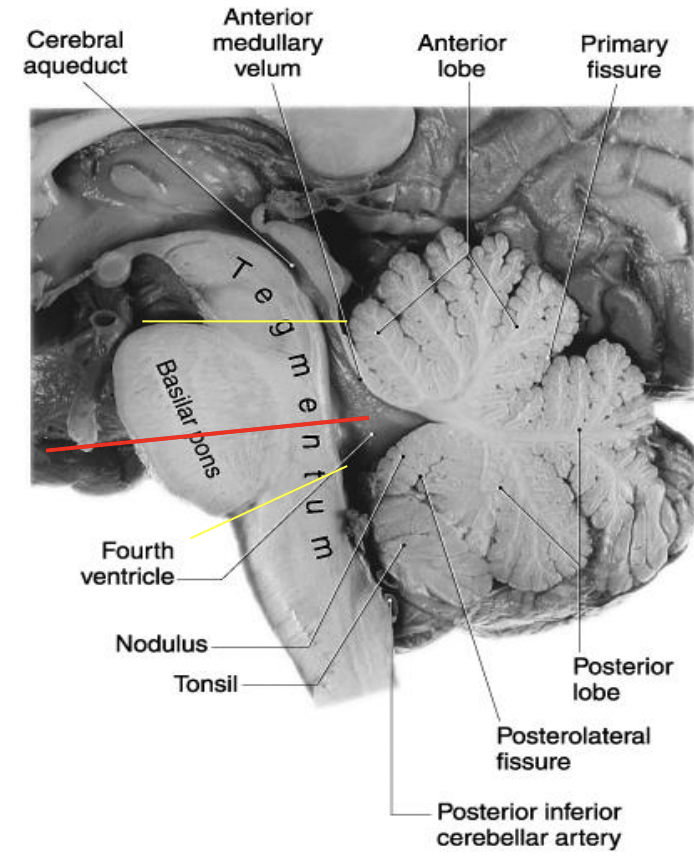

Midsagittal view

Midsagittal: pons

two regions: tegmentum and basilar